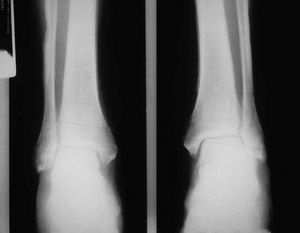

En el estudio completo de extensión, la radiología ósea demostró una evidente reacción perióstica bilateral en tibias, peronés y fémures, junto con unas imágenes densas sugestivas de metástasis óseas en ambos fémures (fig. 2). Un electromiograma practicado demostró la presencia de una típica polineuropatía axonal con potenciales de baja amplitud, tanto motores como sensitivos. Finalmente, la gammagrafía ósea con tecnecio-99m puso de manifiesto un aumento de captación poliarticular, así como lineal, en los huesos largos, más evidente en la diáfisis del fémur izquierdo, dando la típica imagen en "doble raíl" de las periostitis. En la gammagra-fía destacaba también la presencia de intensos focos de captación en el húmero y el radio derechos, ambos fémures y tibias, sugestivos de metástasis óseas concomitantes (fig. 3).

Figura 2. Radiografía anteroposterior de tibias y peronés donde puede observarse una reacción perióstica bilateral y un engrosamiento de la cortical.